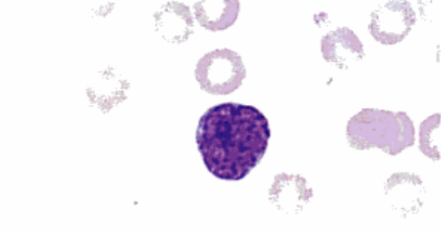

Monoblasto La célula presenta una relación núcleo:citoplasma aumentada, citoplasma y núcleo basófilos, también se observan nucleolos (Rodak, 2004). Fuente: Rodak, E. (2004). Hematología: Fundamentos y Aplicaciones. (2da ed.). Madrid, España: Editorial Médica

Promonocito La célula ha disminuido bastante su tamaño en comparación con el monoblasto, es redonda y su núcleo céntrico y basófilo ya no presenta nucleolos, el citoplasma ha aumentado la acidofilia. La relación núcleo citoplasma ha disminuido en comparación al monoblasto (Rodak, 2004). Fuente: Rodak, E. (2004). Hematología: Fundamentos y Aplicaciones. (2da ed.). Madrid, España: Editorial Médica

Monocito (maduro) Son también llamados histiocitos, se suelen encontrar en tejidos, donde se les llama macrófago, más que en sangre periférica. La célula posee un núcleo céntrico basófilo, con forma de "frijol", el citoplasma es acidófilo y escaso (Rodak, 2004). Fuente: Rodak, E. (2004). Hematología: Fundamentos y Aplicaciones. (2da ed.). Madrid, España: Editorial Médica